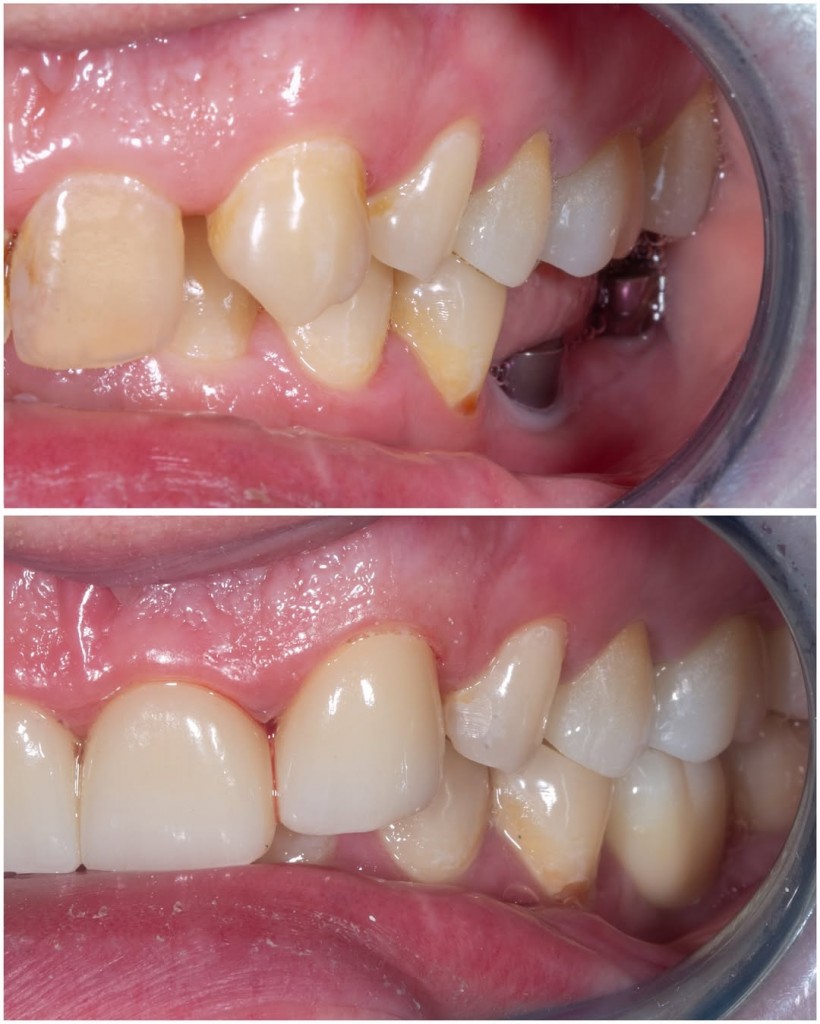

В данном клиническом случае мы показываем как можно эстетически подкорректировать врожденные аномалии. У пациента с рождения отсутствуют вторые резцы, их место заняли клыки.

Визуально мы видим несоответствие формы,  наличие промежуткав между зубами, а также дисколорит.

Было предложено исправить данный дефект с помощью коронок из диоксида циркония.